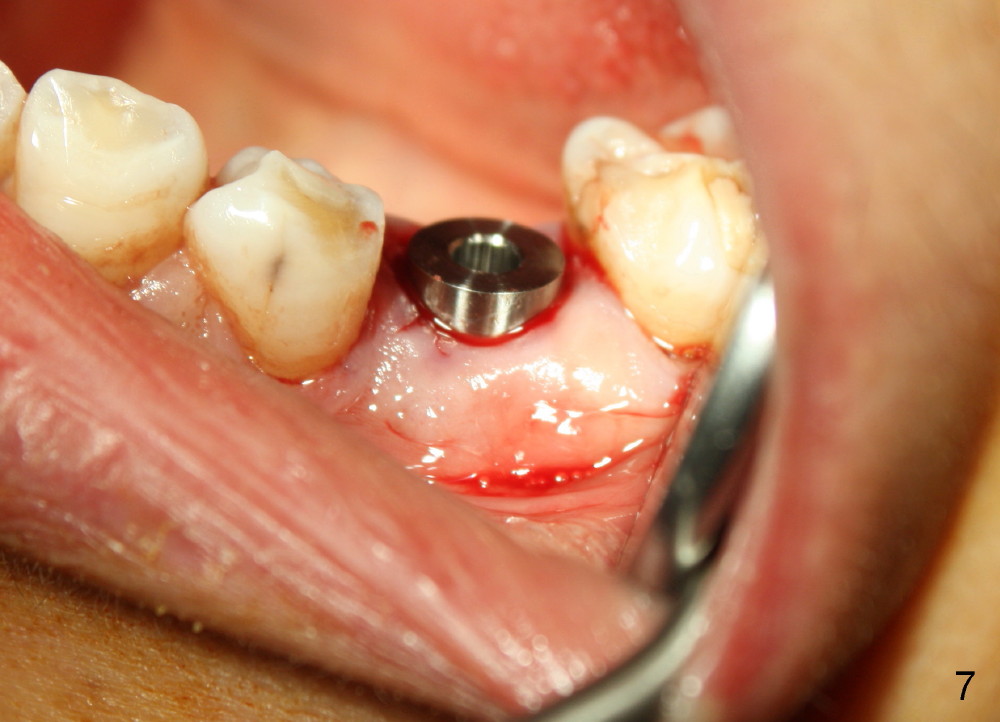

Taking multiple intraop X-ray is also necessary for depth adjustment (Fig.3-5).  For example, when a 5x20 mm tap is inserted at the depth of 17 mm, it is close to the mental loop (Fig.4), whereas the binding to the bone is minimal.  So a larger implant is to be placed at a shallower depth (Fig.5: 6x17 mm with insertion torque >60 Ncm).  The shallower implant placement creates limited space for future abutment and crown (Fig.6,7).  A short abutment will be used and the implant margin will be prepared as low as possible.  As expected, the wound heals in a week (Fig.8).

Six months postop, bone density around the implant increases (Fig.9).  There is slight gingival recession buccal to the implant (Fig.10 arrow).  A short abutment is placed and prepared short (Fig.11 A); the margin is prepared as low as possible in the implant (I).